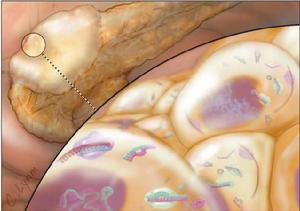

黃體囊腫粒層黃體囊腫:此種最為常見,來自黃體的血腫,可發生於育齡期。直徑2.5-6cm不等,最大可達11cm;大於4cm的少見,囊腫向卵巢表面突起,早期可似血腫,卵巢表面呈紅褐色,內為透明或褐色漿液,囊壁淺黃色,呈特徵性花環狀。

粒層黃體囊腫:此種最為常見,來自黃體的血腫,可發生於育齡期。直徑2.5-6cm不等,最大可達11cm;大於4cm的少見,囊腫向卵巢表面突起,早期可似血腫,卵巢表面呈紅褐色,內為透明或褐色漿液,囊壁淺黃色,呈特徵性花環狀。

黃體囊腫為發生於單側卵巢的孤立性囊腫,表面光滑,呈琥珀色,直徑很少大於4cm,罕見超過8cm。但文獻曾有報導達11cm。單房性,壁薄,半透明。切面可見中央腔內含有淡黃色、嗜紅色液體或凝血塊,囊壁部分或全部為黃色,有時捲曲成花環狀。